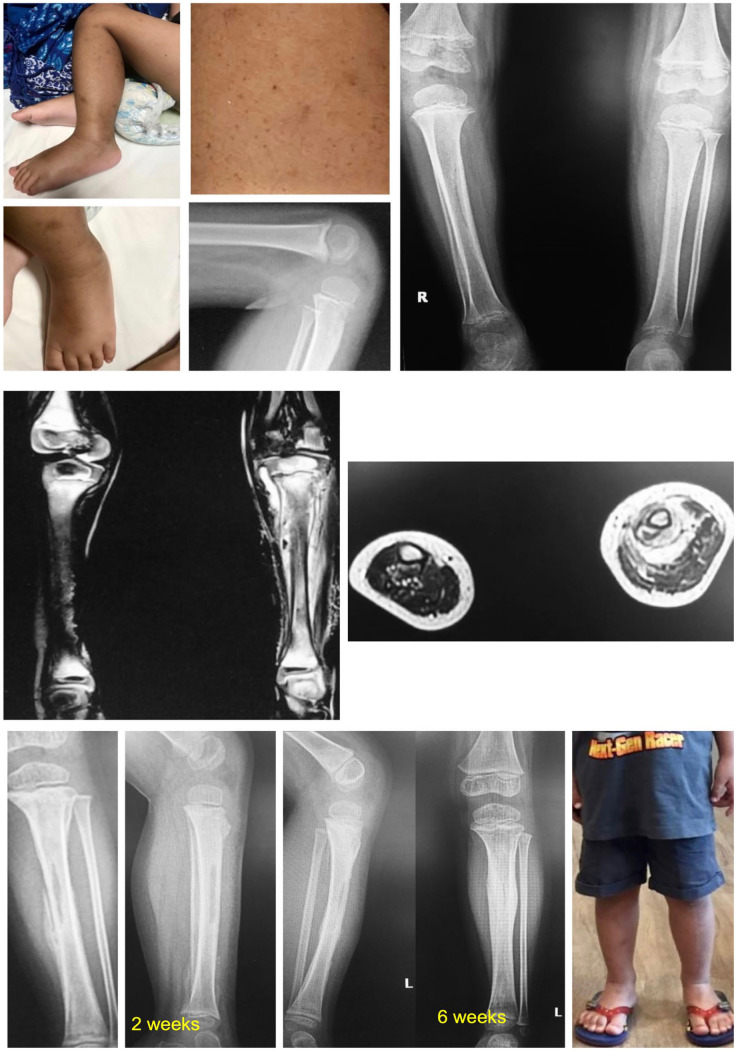

Results: Eighteen cases (17 males, 1 female) of scurvy were referred to our institution. Thirteen of 18 patients were misdiagnosed before referral. The median age at presentation was 4.5 (range, 2-11) years. The average body mass index was 13.93 ± 0.63 kg/m2. Half of patients had healthy weight. All patients presented with lower limb pain and 17 of 18 with refusal to walk. The median onset of diagnosis was 11 (range 4-48) weeks. White line of Frankel was described in all patients. Seven had anemia and 6 of 18 had increase in erythrocyte sedimentation rate and/or C-reactive protein levels. Only one patient had ascorbic acid levels evaluation before treatment since it was not readily available in our country. Treatment length varied from 2 weeks to 6 months.

Abstract Image